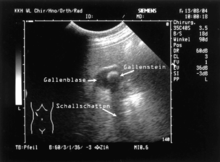

Die Gallenblase (lateinisch Vesica fellea bzw. Vesica biliaris; von lateinisch vesica „Blase“, und fel bzw. bilis „Galle“) ist ein Hohlorgan der Wirbeltiere. In ihr wird die Galle, die von der Leber für die Verdauung von Fetten im Darm produziert wird, eingedickt und gespeichert. Umgangssprachlich wird auch die Gallenblase selbst oft als „Galle“ bezeichnet. Häufige Erkrankungen sind von Gallensteinen verursachte Behinderungen des Zu- und/oder Abflusses der Gallenblase (Cholecystolithiasis und Choledocholithiasis) und durch Gallensteine ausgelöste Entzündungen der Gallenblase (Cholezystitis). Die Gallenblase muss (beim Menschen) dann oft chirurgisch entfernt werden (Cholezystektomie). Das verbreitetste Untersuchungsverfahren zur Beurteilung der Gallenblase ist die Sonografie.

Gallensteine sind Ausfallprodukte aus der Gallenflüssigkeit. Bei etwa 12 % der deutschen Bevölkerung treten diese Konkremente auf, werden aber nur bei ungefähr der Hälfte der Betroffenen symptomatisch. Die Ursachen können zum Beispiel in einem Ungleichgewicht der Gallenbestandteile Gallensäure und Cholesterin liegen. Geht Gallensäure aufgrund unzureichender Resorption dem enterohepatischen Kreislauf verstärkt verloren, wie zum Beispiel bei Morbus Crohn, oder wird unzureichend gebildet, so nimmt der Cholesterinanteil relativ zu. Dies gilt auch für einen erhöhten Cholesterinspiegel im Blut (Hypercholesterinämie). An den Kristallisationskern lagern sich nachfolgend weitere Substanzen an, was zur Cholelithiasis (Gallensteinleiden) führen kann. Besonders wenn sehr junge Menschen stark betroffen sind, kann die Ursache auch in einer Aufbaustörung des roten Blutfarbstoffs (Porphyrie) liegen, dessen Vorläuferprodukte die Gallenkanalzellen schädigen.

Zur apparativen Untersuchung der Gallenblase und der Gallenwege sowie eventueller krankhafter Erscheinungen steht eine Vielzahl von Verfahren zur Verfügung. Von diesen ist die Sonografie die verbreitetste, da sie einfach durchzuführen und für den Patienten risikofrei ist. Somit ist die Sonografie das erste Verfahren zur Beurteilung der Gallenblase, an das sich gegebenenfalls weitere Untersuchungen anschließen. Die Untersuchung wird üblicherweise am nüchternen Patienten durchgeführt, da dann die Gallenblase gefüllt und am besten zu beurteilen ist.[11]